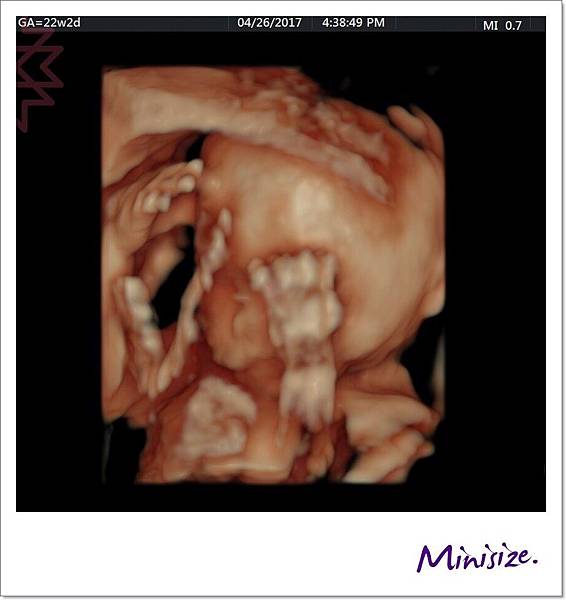

手

剛好我的寶寶手手有摺起來

技術師用兩種不同角度拍照

檢查時會細數1、2、3、4、5 五支手指頭

下兩張左圖都是大拇指 右圖是其餘四指

手指看起來很修長應該是遺傳麻麻

腳

腳趾就比較容易照啦

左右各是五隻腳趾頭

腳掌也發育良好